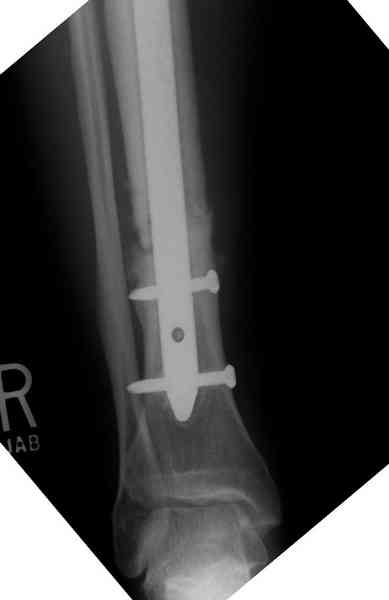

Недавно на нашей ежемесячной Morbidity&Mortality conference мы

разбирали похожий случай, ложный сустав большеберцовой кости после

резекции опухоли.

К нашему онкологу-ортопеду обратился больной с жалобами на боли в

голени, из рассказа - год назад была сделана биопсия большеберцовой

кости, но название заболевания "не запомнил".

Оперирован в военном госпитале с заменой сегмента аллокостью

большеберцовой кости и после демобилизации явился для постоянного

наблюдения по месту жительства.

Наши имели проблему со сращением, пришлось им сделать динамизацию,

дополнительную аутопластику.

Снимки представлены.

Имя     : 1 adamantioma ap orig.jpg